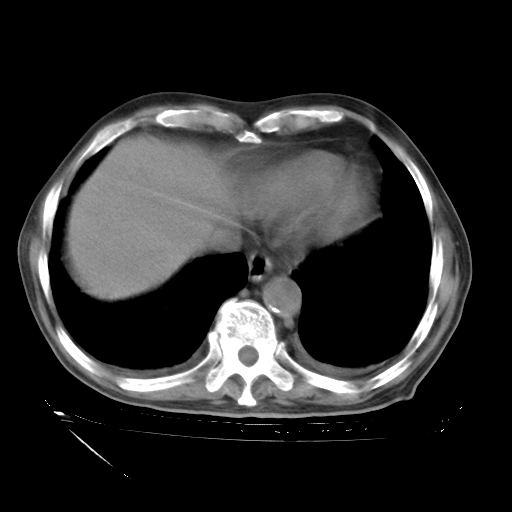

甲强龙80mg/日+抗结核治疗(异烟肼+利福霉素+乙胺丁醇)10天。复查肺部CT。

治疗10天肺部CT

补充下:5月9日胸部CT:似乎已见双下肺胸腔积液了,鉴于目前有下肢水肿,肝功示:白蛋白低,应注意多浆膜腔积液(漏出液可能大?),需注意!